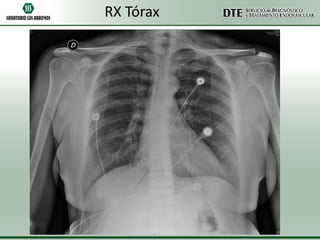

RX Tórax